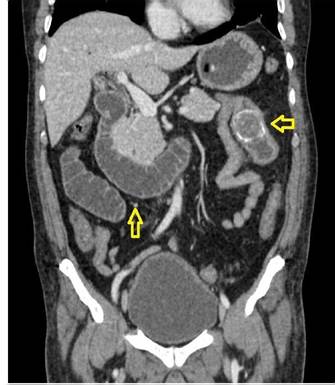

Fuente: examen del paciente realizado en centro de diagnóstico por imágen extrainstitucional.

Figura 4. Tomografía axial computarizada de abdomen con contraste (corte coronal) que evidencia presencia de cálculo a nivel de yeyuno (fecha) y asas de intestino dilatadas (flecha).

En dicha institución se revalora al paciente, evidenciando al examen físico mal estado general, consciente, orientado, con signos de dificultad respiratoria y desaturación al aire ambiente hasta 70%, saturación hasta 92% con oxígeno por máscara con reservorio a 8 l/min, piel y mucosas moderadamente secas, normocoloreadas, pulmones con murmullo vesicular disminuido con estertores y roncus diseminados en ambos campos pulmonares, abdomen levemente distendido, con ruidos hidroaereos (+) hipoactivos, blando, doloroso a la palpación profunda en mesogastrio, sin datos de irritación peritoneal, tacto rectal con esfínter normotónico, ampolla rectal vacía y dedo de guante explorador limpio, siendo el resto del examen conservado. Se obtienen estudios complementarios de laboratorios en sangre que reportan: leucocitosis de 10 640/ml, con neutrofilia del 88 %, Hb 12 g/ dl (previo de 15,2), normocítica, normocrómica, Hto 34,8 %, hipoproteinemia con hipoalbuminemia severa con proteínas totales de 4,2 g/dl y albumina de 2,1 g/dl, e hipokalemia leve con K de 3,0 mEq/L, además de gasometría arterial que evidenciaba alcalosis metabólica parcialmente compensada con acidosis respiratoria, con insuficiencia respiratoria aguda hipoxémica moderada (PaFiO2 170), y resto de laboratorios del hemograma, coagulograma, glicemia, pruebas renales y hepatograma dentro de parámetros normales. Se obtiene a la vez Rx de tórax PA y abdomen AP de pie, evidenciando en el primero imágenes radiopacas de infiltrado alveolo-intersticial diseminadas en ambos campos pulmonares a predominio del lado izquierdo, y en la segunda, asas de intestino delgado dilatadas con imagen sugestiva de pila de monedas y niveles hidroaéreos a predominio del lado izquierdo (Figura 1). Tras la obtención de estos exámenes y en el contexto del paciente se han tomado en cuenta los diagnósticos diferenciales de obstrucción intestinal vs hemorragia digestiva alta, este último según la institución inicial que realizó la referencia, que indicaba la presencia de vómitos porráceos y el evidente descenso de la Hb en 3 puntos, por lo que se continúa con la indicación de endoscopia digestiva alta la cual reporta: “Datos de obstrucción intestinal alta (debito de retención proveniente de segunda y tercera porción duodenal) (Figura 2), sospecha de metaplasia columnar de esófago, gastritis crónica superficial de antro, estudio parcialmente satisfactorio (por segmentos con debito retentivo no valorables)”. Con estos hallazgos se refuerza mucho más la primera hipótesis, pero llama la atención que un paciente sin antecedentes quirúrgicos abdominales presente datos de obstrucción intestinal, además de tratarse de un paciente con un cuadro clínico atípico, y que al momento no había podido ser resuelto bajo medidas conservadoras, por lo que se decide solicitar estudios ampliados extrainstitucionales, como una tomografía axial computarizada (TAC) de abdomen con contraste de forma urgente; tras gestionar la misma, se obtiene reporte que indica (Figuras 3y4): “Hallazgos tomográficos compatibles con íleo biliar (imagen de cálculo de 4 x 3,2 cm con áreas de calcificación en su pared a nivel de yeyuno proximal), probable fístula bilio-digestiva (colecistoduodenal), neumobilia, pequeños quistes renales simples bilaterales, hallazgos de la porción valorable de tórax sugerente de proceso infeccioso de etiología viral sugestivas de COVID-19”. Con ello se solicita la valoración por el servicio de cirugía que, en misma fecha de ingreso, realiza procedimiento quirúrgico de laparotomía exploradora, enterotomía, extracción de cálculo y enterorrafia, con diagnóstico postoperatorio de “Obstrucción intestinal alta, íleo biliar, neumonía por SARS-COV2, hiperplasia prostática”, describiendo en los hallazgos operatorios un cálculo de aproximadamente 4 x 4 cm que ocupaba la totalidad de la luz yeyunal a +/- 60 cm del ángulo de Treitz.